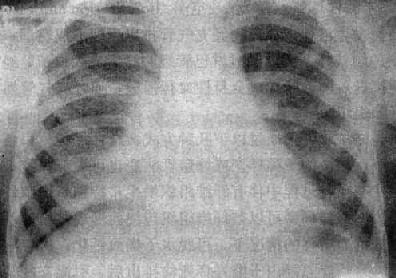

由于病灶系多次血行播散所形成,故X线表现为大小不一、密度不同、分布不均的多种性质的症灶(图3-1-23)。小者如粟粒,大者可为较大的结节状,主要分布于两肺上、中野,下野较少。早期播散的症灶可能已经钙化,而近期播散的病灶仍为增殖性或渗出性。本型结核发展较慢,经治疗新鲜病灶可以吸收,陈旧病灶多以纤维钙化而愈合。恶化时病灶可融合并形成空洞或逐渐转为慢性纤维空洞型肺结核

慢性血行播散型肺结核

图3-1-23 慢性血行播散型肺结核

两肺野布满大小不一、密度不同、分布不均的病灶,

下野较少,膈位置低而平